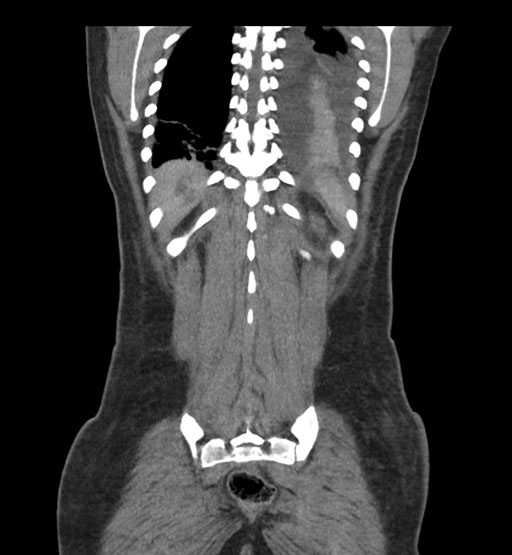

Coronal Arterial

Coronal Venous

Imaging analysis

Based on initial findings, which issue(s) would you be most concerned about?